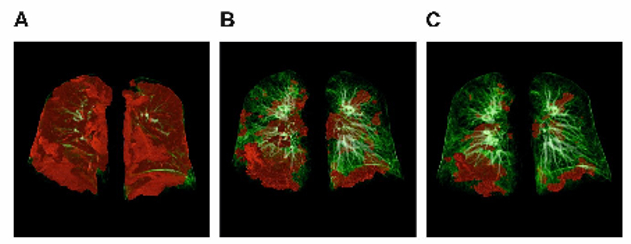

- Cardiopulmonary recovery after COVID-19 – an observational prospective multicentre trial, including software-based pneumonia quantification

- Evaluation of artificial intelligence in thoracic imaging: lung nodule detection, coronary calcium evaluation, measurement of aortic diameters, emphysema quantification and pneumonia quantification

- Texture analysis and quantification in interstitial lung disease

Image processing and analysis, including rapid prototyping based on radiological data, represent core interests and tasks, including multidimensional visualisation, the quantification of disease patterns based on texture analysis, shape analysis and others. Moreover, our new micro-CT core facility allows depiction of structures on μm scale in all three spatial dimensions.